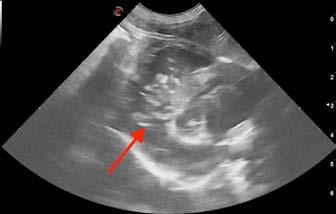

On ultrasound, the liver was enlarged with a diffuse patchy parenchyma (Figure 1). There was sonographic evidence of renal cysts, splenic nodules, and pancreatic changes consistent with chronic pancreatitis. The cause of vomiting and diarrhoea remained open, but due to hepatic changes, fine needle aspirates of liver were taken and submitted for cytology.

Sheba was provided flow-by oxygen and a thoracic point of care ultrasound was performed. The LA:Ao ratio was 1.7 indicating mild left atrial enlargement; there were occasional B lines present, and pleural space disease was excluded based on the absence of pleural effusion and pneumothorax (glide sign present). Surprisingly, there were a number of segments of hyperechoic, parallel lines within the right ventricle, indicative of heartworm infection. The finding was supported by a positive heartworm antigen test.